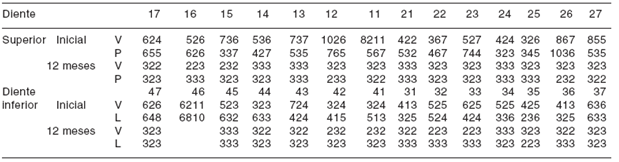

Se obtuvieron resultados de profundidad al sondeo, 12 meses posterior a la terapia periodontal ( Cuadro II), y se evaluaron los hallazgos radiográficos 12 y 24 meses después ( Figura 5 ).

V: vestibular P: palatino L: lingual

Cuadro II Profundidad al sondeo inicial y 12 meses posterior al tratamiento periodontal.